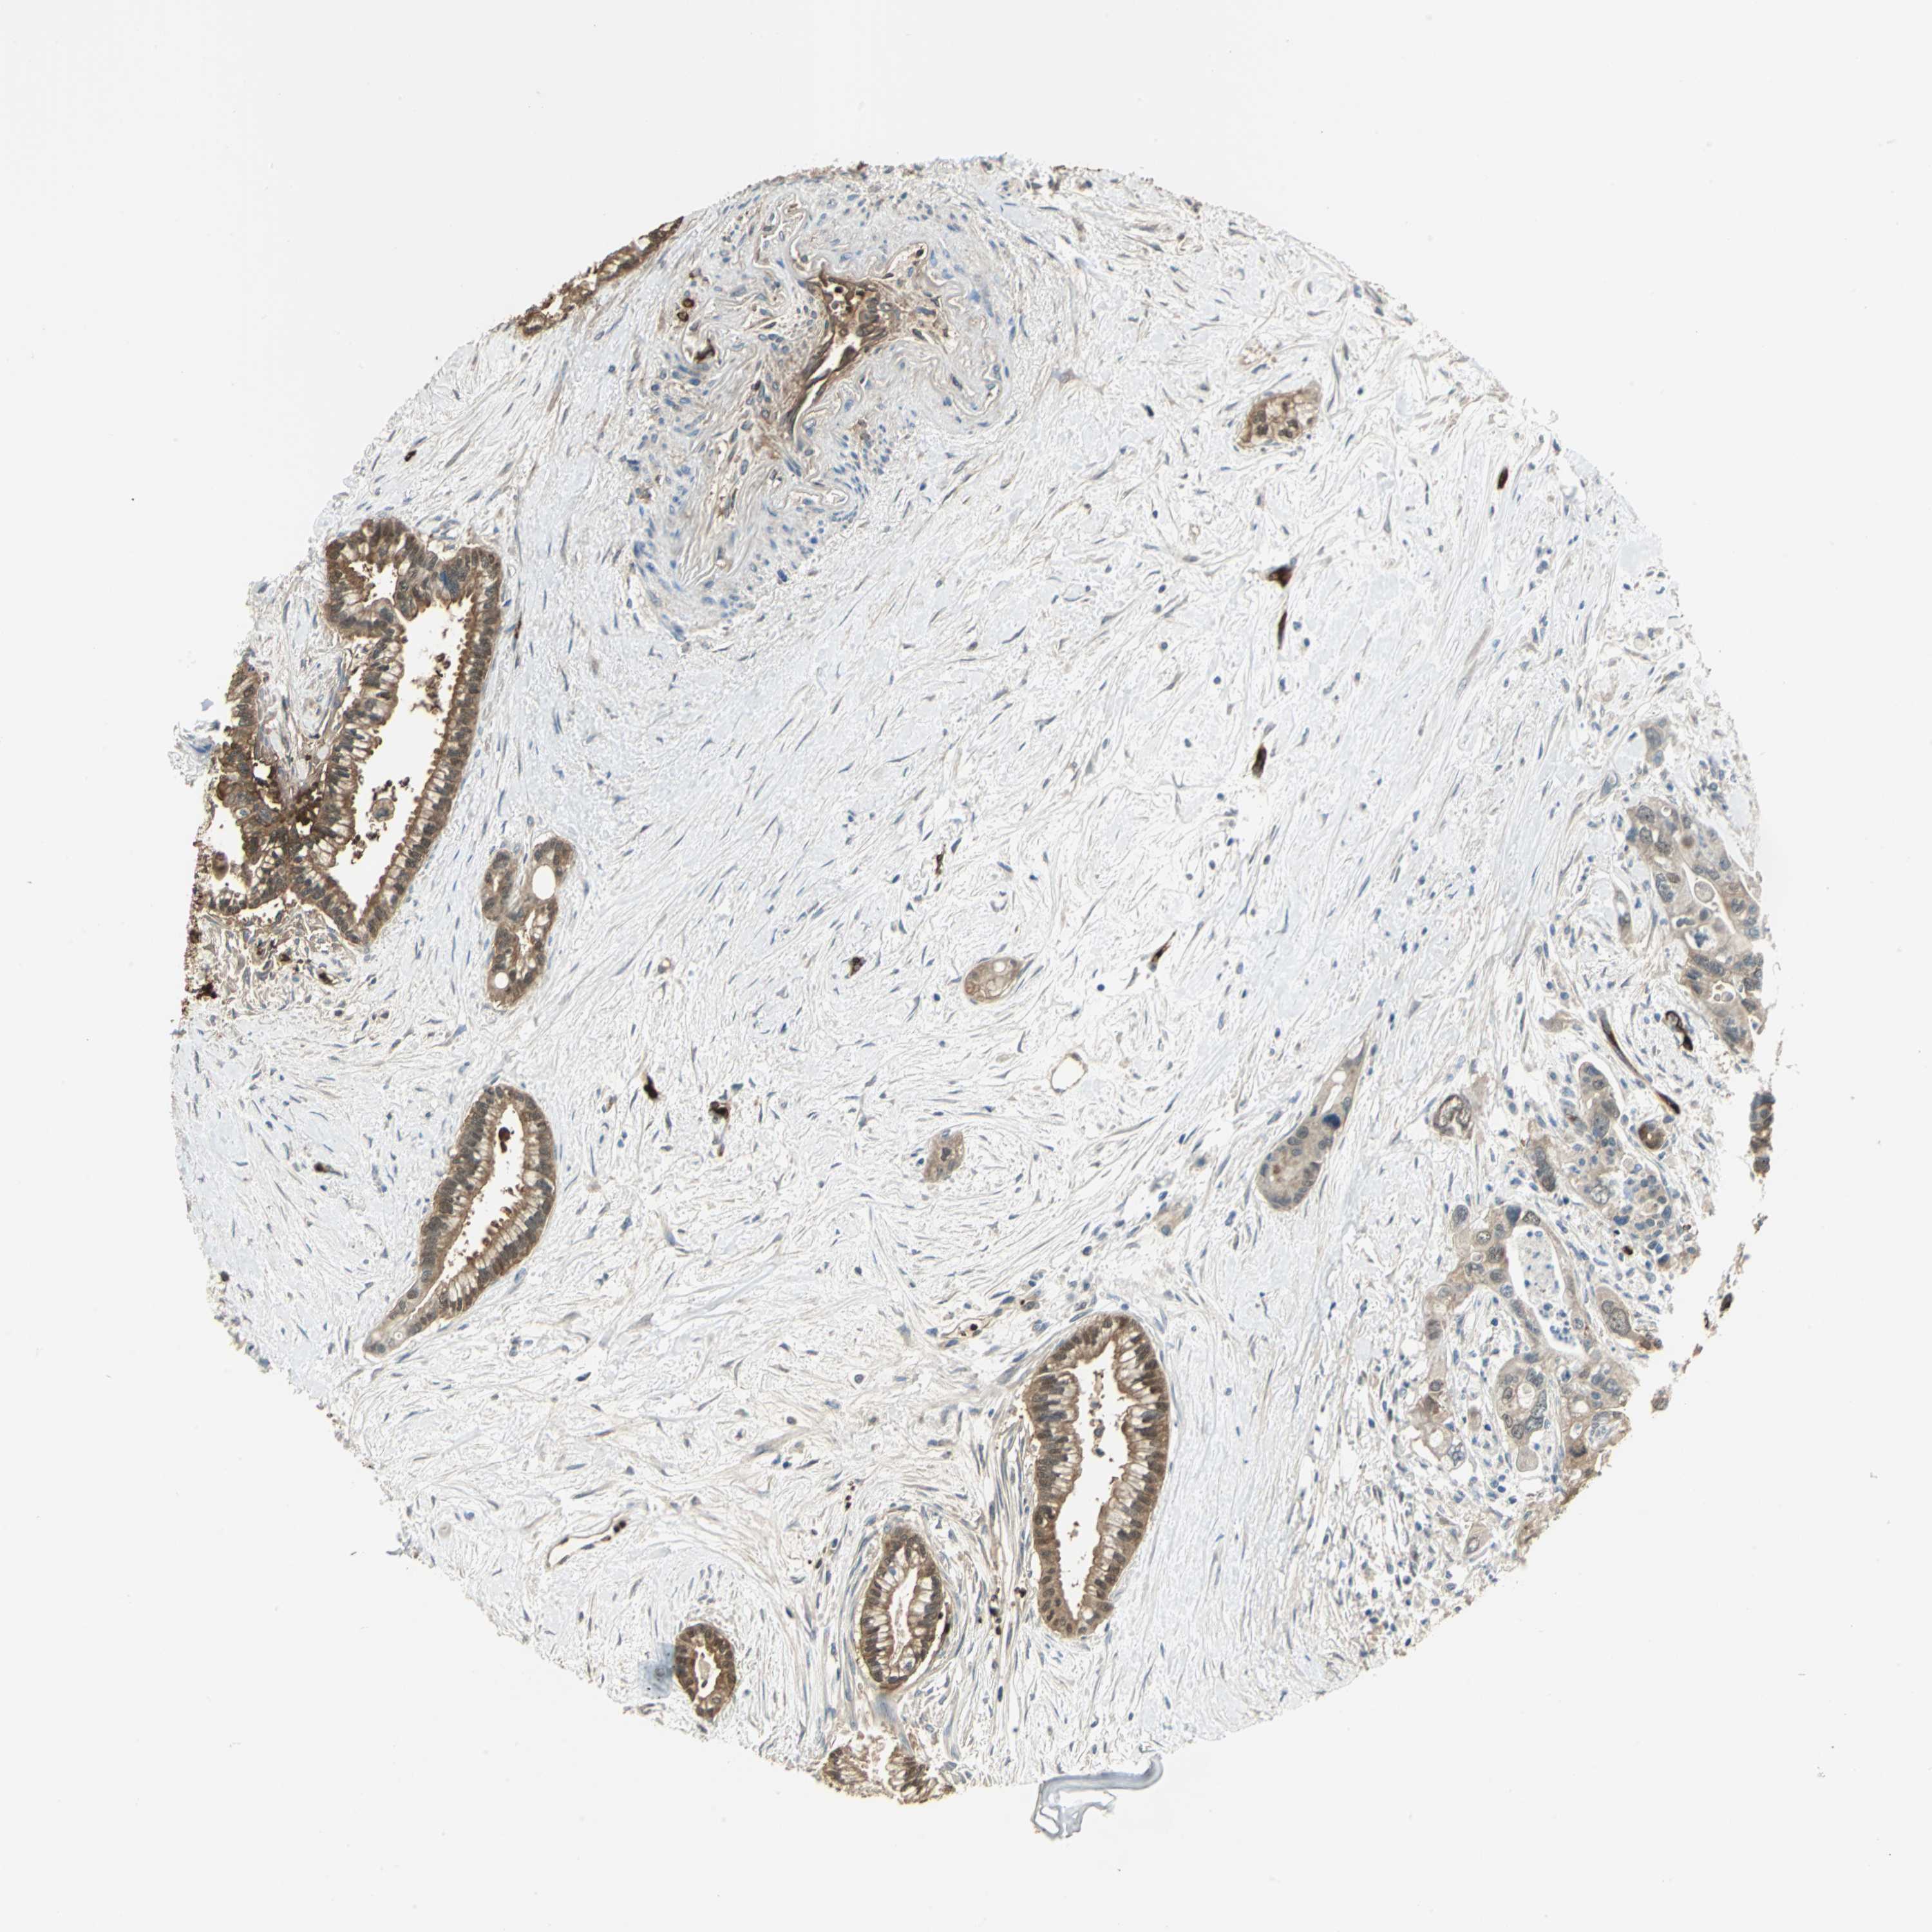

PANCREATIC CANCER - Protein expressioni

A mouse-over function shows sample information and annotation data. Click on an image to view it in a full screen mode. Samples can be filtered based on level of antibody staining by selecting one or several of the following categories: high, medium, low and not detected. The assay and annotation is described here.

Note that samples used for immunohistochemistry by the Human Protein Atlas do not correspond to samples in the TCGA dataset.

Antibody stainingi

Antibody staining in the annotated cell types in the current human tissue is reported as not detected, low, medium, or high, based on conventional immunohistochemistry profiling in selected tissues. This score is based on the combination of the staining intensity and fraction of stained cells.

Each image is clickable and will lead to virtual microscopy that enables deeper exploration of all samples and also displays staining intensity scores, fraction scores and subcellular localization as well as patient and tissue information for each sample.

Antibody HPA006308

Antibody HPA071064

Staining

High

Medium

Low

Not detected

Intensity

Strong

Moderate

Weak

Negative

Quantity

>75%

75%-25%

<25%

None

Location

Nuclear

Cytoplasmic/membranous

Cytoplasmic/membranous,nuclear

Adenocarcinoma, NOS

Adenocarcinoma, metastatic, NOS